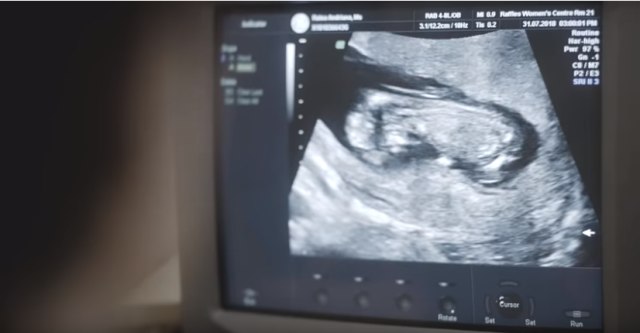

Usia Kehamilan

Dokter menggunakan beberapa petunjuk untuk mengetahui usia kehamilan, yatu sejak kapan pertama kali detak jantung janin dapat didengar dengan alat doppler, dari tanda kehidupan janin yang mulai terasa, dari tinggi fundus dan berdasarkan pemeriksaan USG.

Berdasarkan usia kehamilan itu, dokter akan menentukan perkiraan waktu Anda bersalin, Moms. Atau, bisa juga memakai rumus Neagle yang dihitung berdasarkan Hari Pertama Haid Haid Terakhir (HPHT): (Hari+7), (Bulan-3), (Tahun+1). Contoh HPHT 5 Juni 2018, maka perkiraan persalinan tanggal 12 Maret 2019